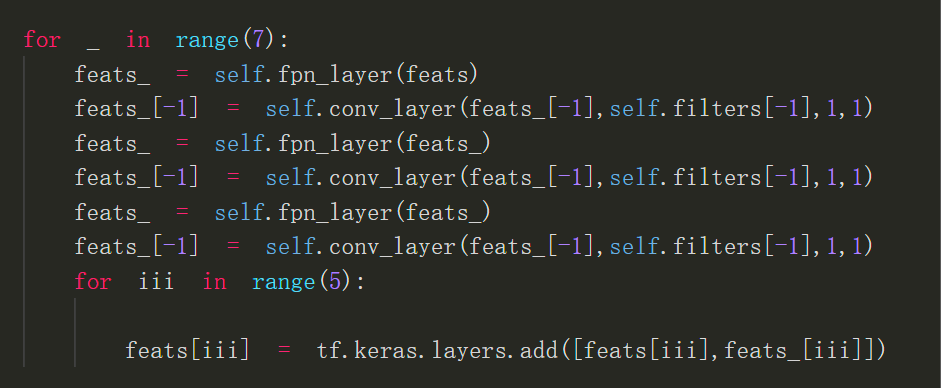

ResFPN结构

ResFPN关键代码

以上便是我此次参加比赛所使用的模型,提交分数为0.633,但此模型其实还可以做些改进,比如将backbone出来的feats继续下采样的resnet换成efficientnet block,ResFPN也可以继续改进到ResFPN2.0,ResFPN里的每层fpn_layer其实就是一次自顶向下融合,ResFPN2.0与第一代ResFPN的区别就是ResFPN2.0每一次自顶向下融合之后最顶上的特征图就进行一次卷积之后再进行下一次融合。

以下是ResFPN2.0关键代码: